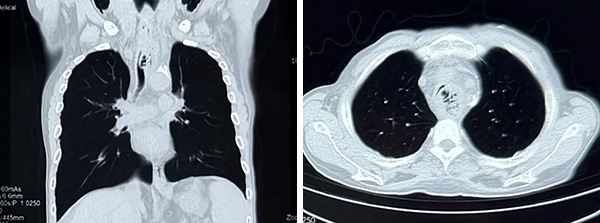

CT可见气管中段管腔严重狭窄伴食管纵隔瘘(左图为矢状位,右图为冠状位)

“气道狭窄程度极高,患者无法脱离氧气,必须立即置入气道支架解除梗阻!”,王洪武主任没有丝毫迟疑,当即表示接受患者转院治疗,并指示呼吸道梗阻抢救绿色通路,同时火速赶往医院。随即通知麻醉科医师王海丽、呼吸科二区值班医师张艳宾做好接收准备,备班医师陈双、护士赵行健及进修医师山萌在接到通知后,均毫不犹豫放弃假期,即刻动身赶往医院集结。W先生及家属赶到急诊室后立即办理住院手续,并快速送到门诊手术室进行抢救。

第二天复查CT,气管狭窄完全缓解,支架位置良好